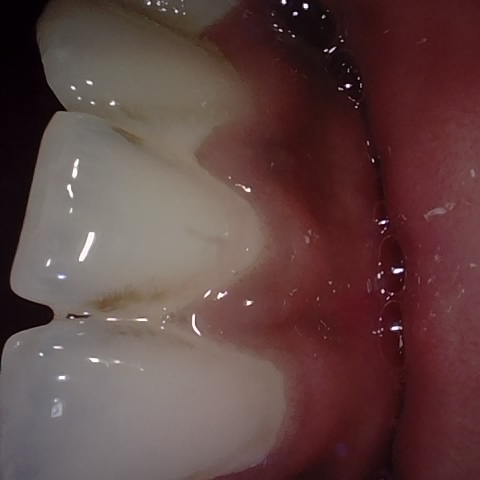

Image 16 / 400

NHD25466

Annotated as "Good"

Original Image Rendering Image